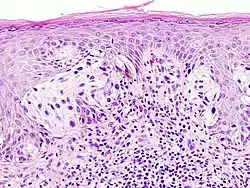

Surgical pathology is the most significant and time-consuming area of practice for most anatomical pathologists. Surgical pathology involves gross and microscopic examination of surgical specimens, as well as biopsies submitted by surgeons and non-surgeons such as general internists, medical subspecialists, dermatologists, and interventional radiologists.

The practice of surgical pathology allows for definitive diagnosis of disease (or lack thereof) in any case where tissue is surgically removed from a patient. This is usually performed by a combination of gross (i.e., macroscopic) and histologic (i.e., microscopic) examination of the tissue, and may involve evaluations of molecular properties of the tissue by immunohistochemistry or other laboratory tests.